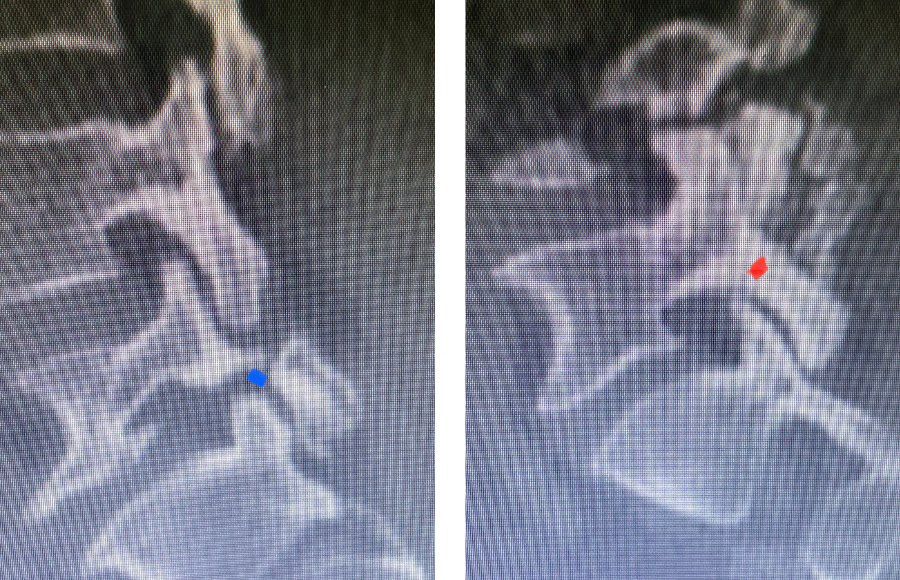

Here is a dramatic example of a patient who had prior laminectomy and fusion surgery four years earlier, and now presents with low back pain with severe burning pain in her right lower extremity pain. She did not respond to epidural steroids. She had a prior L3-S1 laminectomy, and an L3-5 instrumented fusion. A current MRI (Fig 4) demonstrated severe L2-3 next segment stenosis due the development of massively hypertrophied or enlarged L2-3 joint complexes. There was also a grade 1 retrolisthesis of L2 on L3 with a large anterior disc osteophyte complex. The configuration of the stenosis was worse in the right lateral recess secondary to the anterior osteophyte and more right-sided facet compression of the thecal sac, correlating with the patient’s right-sided symptoms. When the anatomy correlates with the patient’s symptoms that is the best set up for success. It was decided to offer a revision surgery to the patient, who agreed.

Fig 4: Sagittal and axial T2-weighted lumbar MRI images demonstrating severe next segment degeneration and stenosis at L2-3 above prior L3-5 fusion. Note retrolisthesis and significant facet arthropathy at L2-3 (red arrow).